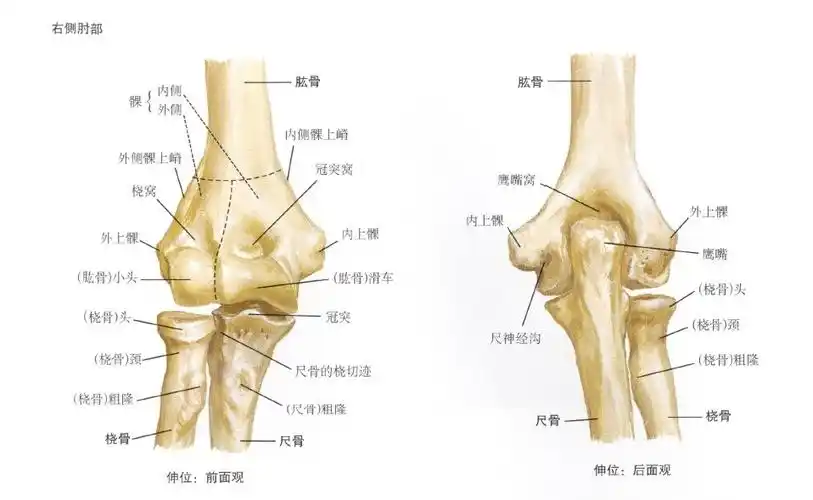

2019--8-26 肘关节x线解剖学